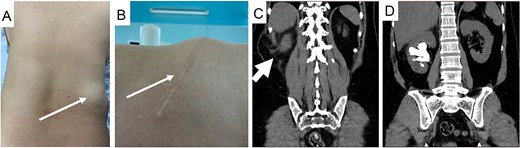

A 50-year-old female presented with a progressively enlarging right lumbar bulge persisting for 3 years following previous open surgery to treat a large staghorn calculus in her right kidney. Examination revealed a visible flank scar and hernia bulge in the supine position (Fig. 1A and B), confirmed by an abdominal computed tomography (CT) scan (Fig. 1C). The CT scan also revealed bowel contents within the sac and a recurrent staghorn right kidney stone (Fig. 1D).

Images of the patient with right flank incision and hernia bulge with clinical picture (A and B, thin arrow), hernia sac on CT scan (C, thick arrow), and staghorn stone (D).